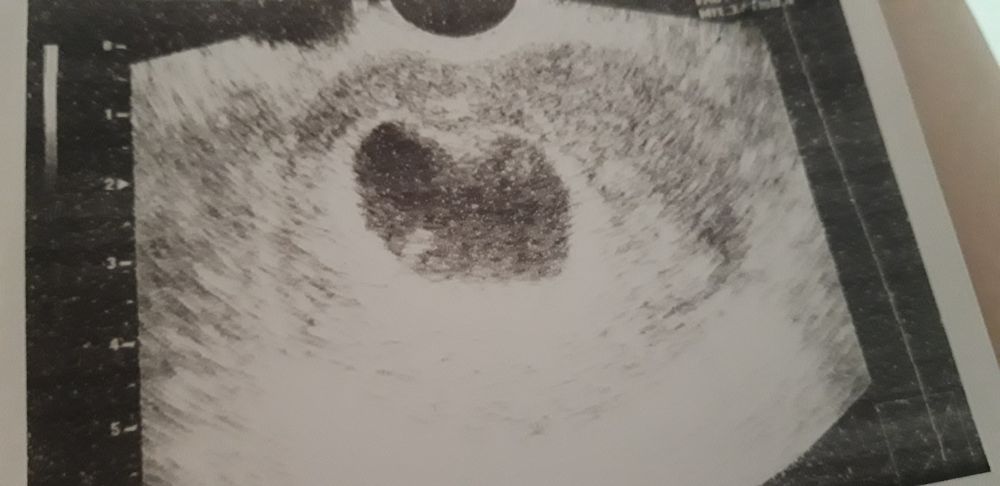

вочки вы можете здесть что нибудь различить? у меня 8 недель 4 дня беременности но мне сказали эмбриона нет.как быть может ли он потом появится??

Я конечно может чего не понимаю, но на снимке узи плодное яйцо не пустое. В 7 недель у меня было то же самое. СБ увидели чуть позже.

Рано. Я помню в 7 недель так же было как переживала. Узи было точь в точь. Пусто это пусто, а тут не пусто!

что за глупости! меня эти узисты иногда вымораживают!!! разве можно такое вот писать. При таких размерах плодного яйца не видно эмбрион! к слову, у меня при таком СВД даже желточного мешочка видно не было. и никто не пугал такими предположительными диагнозами. Беременность малого срока это называется. А через 7-10 дней уверяю вас будет всё видно у вас! Что за узист, такое не редко бывает, такое сплошь и рядом! просто еще рано для эмбриончика. ПОВЕРЬТЕ. успокойтесь!

Рано плакать, еще всё вполне может оказаться в порядке. Сейчас по УЗИ ставят 5 недель- ну так и картинка соответствует 5 неделям, рано еще для эмбриончика. А разбежка со сроком по месячным и даже по предполагаемой овуляции бывает довольно часто- да хотя бы за счет имплантации поздней могло такое получиться. Тем более, вы пишете, что две недели назад еще не было ничего в матке- а теперь-то есть и растёт неплохо, получается, и желточный мешочек есть- а это косвенный признак того, что должен и эмбрион развиваться. Ждите- мне кажется, через 10 дней услышите сердечко